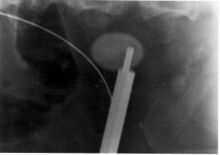

Extracorporeal shock wave lithotripsy (ESWL) is a noninvasive technique for the removal of kidney stones. Most ESWL is carried out when the stone is present near the renal pelvis. ESWL involves the use of a lithotriptor machine to deliver externally applied, focused, high-intensity pulses of ultrasonic energy to cause fragmentation of a stone over a period of around 30–60 minutes. Following its introduction in the United States in February 1984, ESWL was rapidly and widely accepted as a treatment alternative for renal and ureteral stones.[106] It is currently used in the treatment of uncomplicated stones located in the kidney and upper ureter, provided the aggregate stone burden (stone size and number) is less than 20 mm (0.8 in) and the anatomy of the involved kidney is normal.[107][108]

For a stone greater than 10 millimetres (0.39 in), ESWL may not help break the stone in one treatment; instead, two or three treatments may be needed. Some 80-85% of simple renal calculi can be effectively treated with ESWL.[7] A number of factors can influence its efficacy, including chemical composition of the stone, presence of anomalous renal anatomy and the specific location of the stone within the kidney, presence of hydronephrosis, body mass index, and distance of the stone from the surface of the skin.[106]

To address these concerns, the American Urological Association established the Shock Wave Lithotripsy Task Force to provide an expert opinion on the safety and risk-benefit ratio of ESWL. The task force published a white paper outlining their conclusions in 2009. They concluded the risk-benefit ratio remains favorable for many people.[106] The advantages of ESWL include its noninvasive nature, the fact that it is technically easy to treat most upper urinary tract calculi, and that, at least acutely, it is a well-tolerated, low-morbidity treatment for the vast majority of people. However, they recommended slowing the shock wave firing rate from 120 pulses per minute to 60 pulses per minute to reduce the risk of renal injury and increase the degree of stone fragmentation.[106]